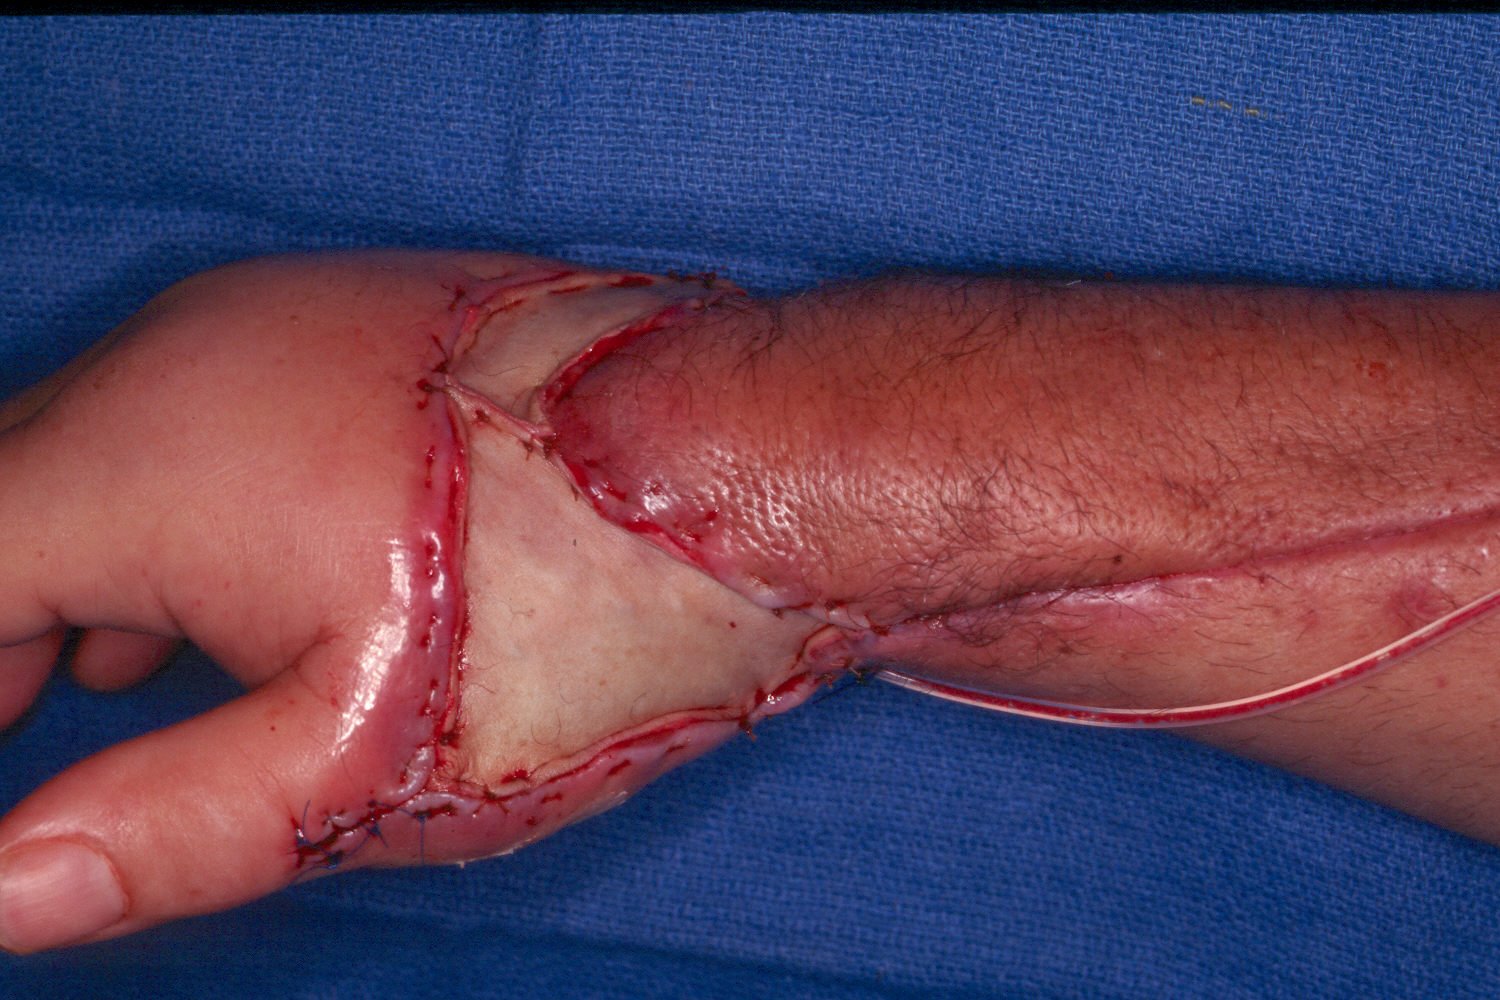

By this point, the patient has undergone proximal row carpectomy for control of infection involving the scaphoid and lunate. The capitate is visible in the depths of the wound:

Further debridement required decortication of the thumb metacarpal (see below). This defect was covered by the abductor pollicis brevis muscle, mobilized distally and rotated to the dorsum of the thumb metacarpal: